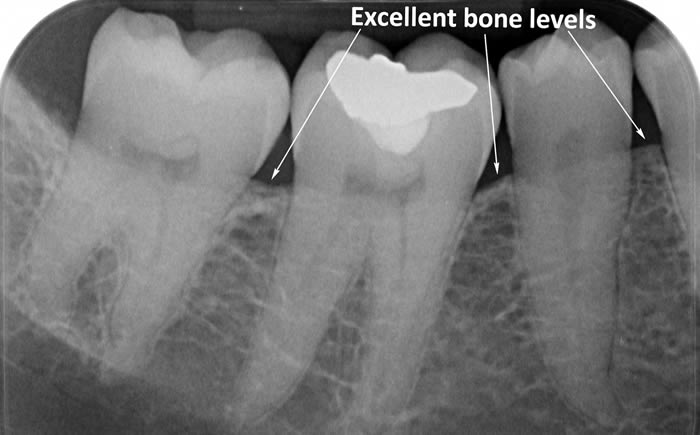

The diagrams below show the different stages of gum disease

Calculus (tartar) is the hard deposit which forms on the teeth in areas where plaque is left undisturbed. Calculus is too hard to brush off with a toothbrush and needs to be removed by the Dental Hygienist with special scaling instruments.

In cases of advanced gum disease our Hygienist’s will also carry out deep scaling which cleans the root surfaces beneath the gum level. When pockets develop in the gums around the teeth plaque bacteria and calculus form on the root surfaces of the teeth and are protected from toothbrushing by the overlying gum. However, our Hygienist’s have special thin scaling instruments which can go down inside the pockets to clean the root surfaces. This treatment is carried out in small sections under local anaesthetic to ensure that you are comfortable throughout the treatment.